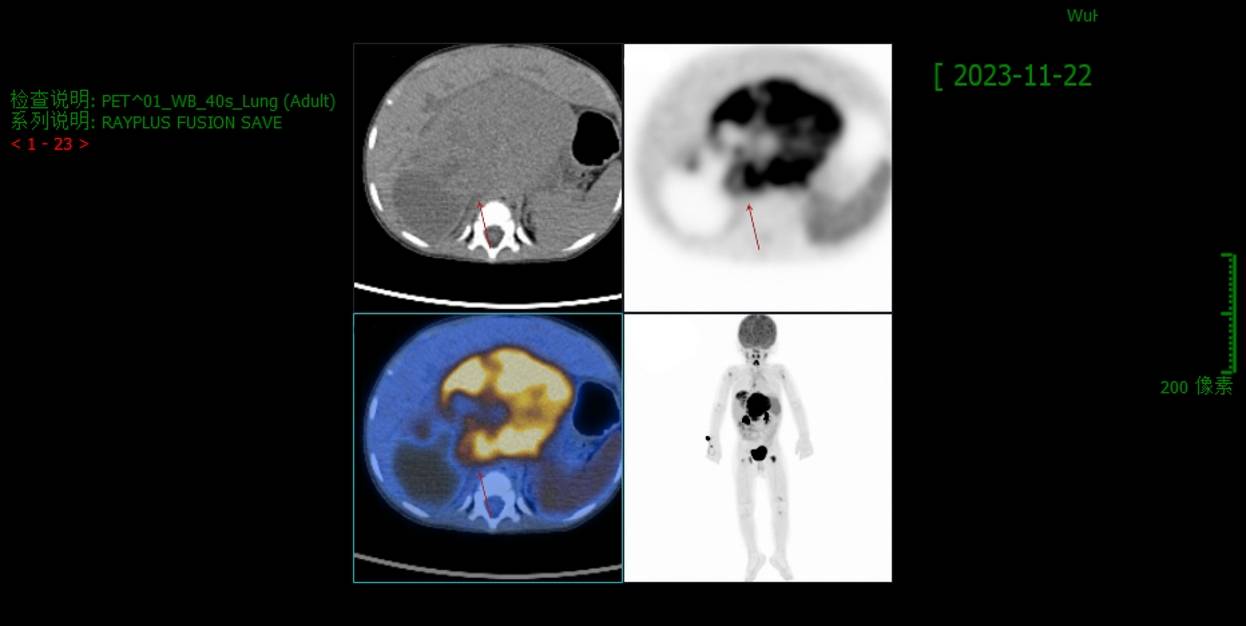

PET/CT(2023.11)

肝门区-腹膜后巨大混杂密度肿块,12.4×6.7cm,边界欠清,内见囊变、点状钙化,实性部分代谢异常增高,邻近肝脏、胰腺、右肾受压并与之分界欠清,右侧肾上腺未见明确显示;肝右叶近膈顶稍低密度肿块,直径约3.9cm,代谢异常增高;多发骨代谢增高灶。上述考虑恶性肿瘤性病变可能性大(神经母细胞瘤伴多发转移?)。